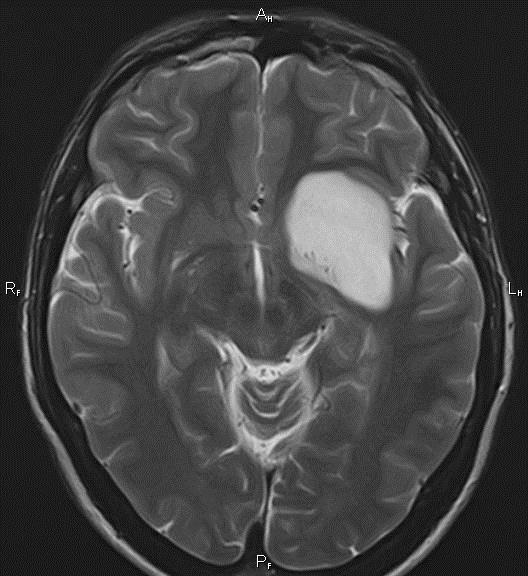

Un quiste cerebral es un saco anormal lleno de líquido ubicado en el cerebro. Puede contener sangre, pus u otro tipo de material. En el cerebro, es posible que un quiste contenga líquido cefalorraquídeo (“CSF”, por sus siglas en inglés). Normalmente ese líquido baña y amortigua el cerebro y la médula espinal. Es frecuente que los quistes cerebrales comiencen a formarse antes del nacimiento.

Un quiste cerebral suele ser benigno (no canceroso). Benigno también quiere decir que el crecimiento no llega a otras partes del cuerpo. Sin embargo, aun cuando un quiste cerebral no sea un cáncer, igualmente puede causar problemas. El quiste puede hacer presión contra el tejido del cerebro y causar síntomas, como dolor de cabeza, problemas de la visión o náuseas.

Quiste pineal. Se presenta en la glándula pineal, en el medio del cerebro. Generalmente este tipo de quiste solo se descubre en un procedimiento de exploración por imágenes que se le realiza a la persona por otra razón. Un quiste pineal usualmente no causa problemas. Si crece mucho, a veces puede afectar la visión. Este tipo de quiste puede aparecer en personas de cualquier edad.

- Resonancia magnética. Esta prueba usa grandes imanes y una computadora para crear imágenes del cuerpo. Las exploraciones de imágenes por resonancia magnética de su cerebro y médula espinal se pueden realizar para obtener más información sobre el quiste y los tejidos cercanos.